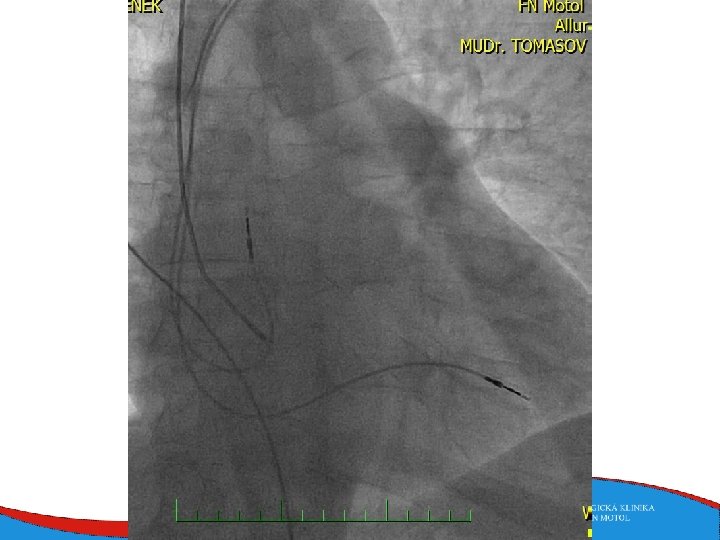

Septal reduction therapy (for ventricular obstruction) • Surgical myectomy • Septal ablation • Symptomatic patients despite the optimal medical therapy • A small amount of alcohol is induced into a septal branch • Myocardial scar and subsequent reduction in the diameter of the basal septum

Therapy Sudden death prevention Based on symptoms and severe systolic dysfunction (EF less than 35% + symtomatologie NYHA II-IV) Heart failure therapy Drug therapy CRT Mechanical assist devices Heart transplant Prevention of thromboembolic complications of atrial fibrillation - NOAC, Warfarin